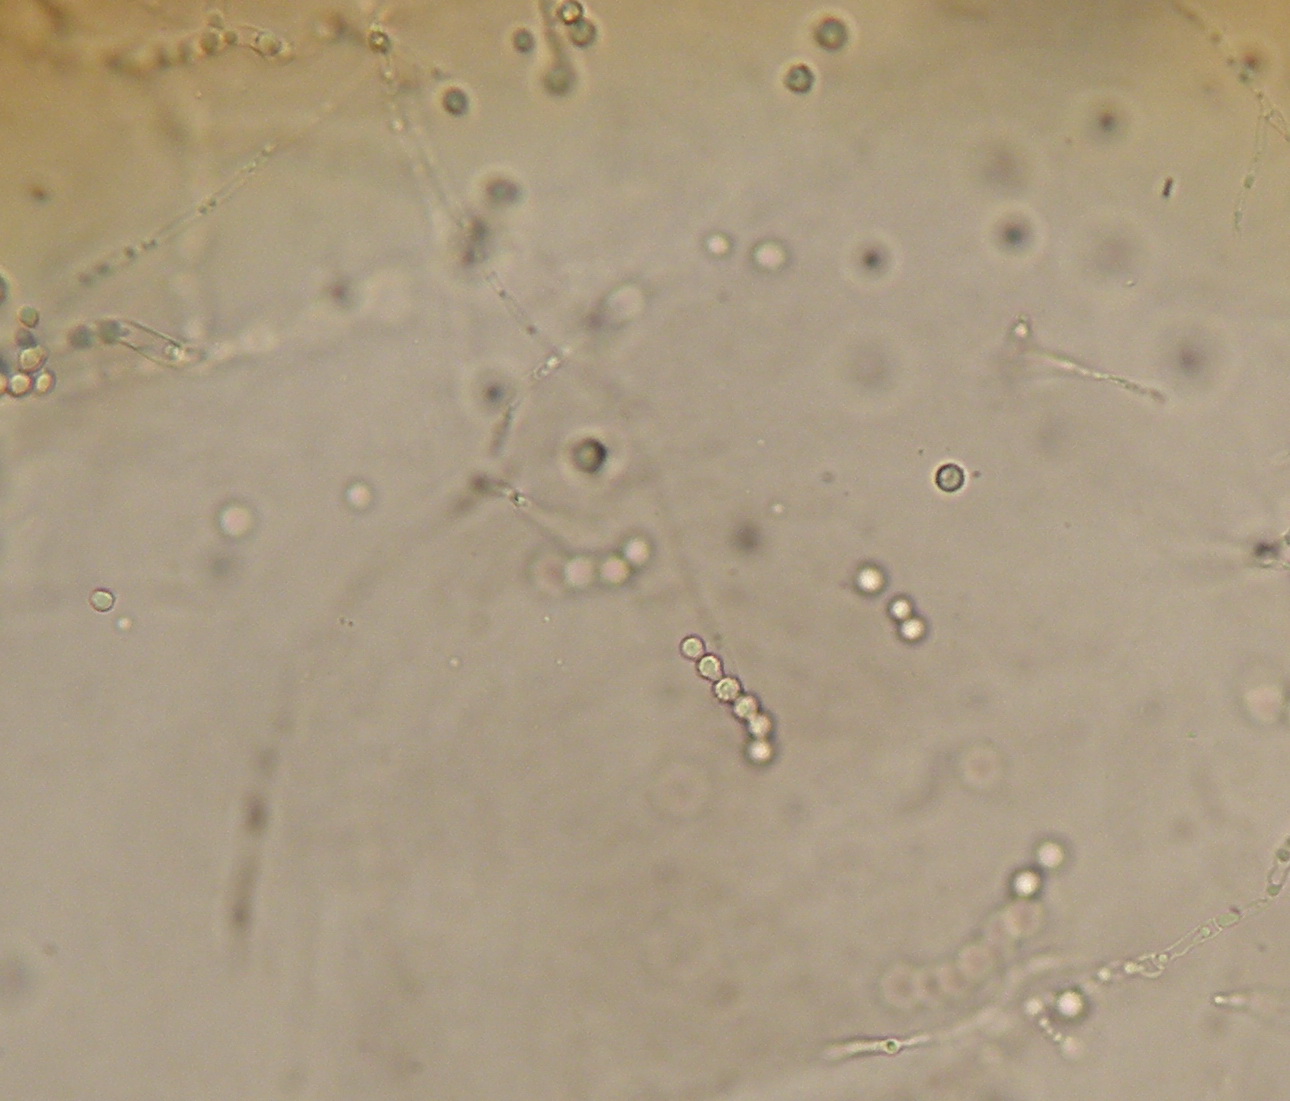

| Células conidiogenas simples ou agrupadas em pincel. Conideos de parede rugosa frequentemente em cadeia. |